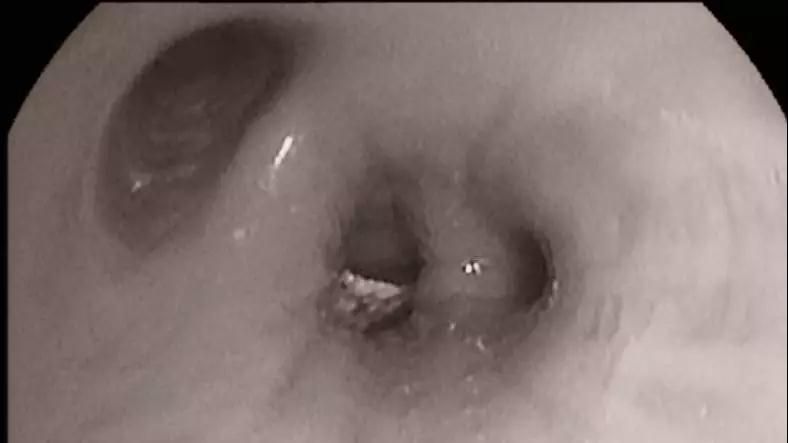

入院第四天,为患者行气管镜检查,于左肺背段外侧段开口见混合型块状物,活检物中见组织及坚硬物质混合,最大硬物直径大于3mm。

左下肺背段分泌物 左下背段 钳出坚硬物质